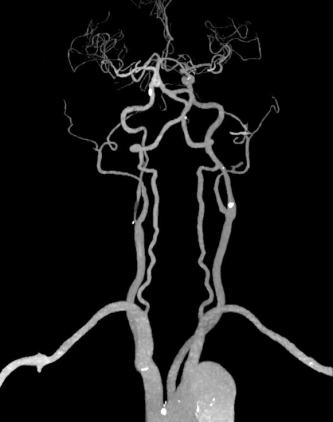

75岁的王大爷(化名)因突发头晕被紧急送往我院救治。入院后,脑病科介入团队为其完善相应检查。头颅磁共振提示右侧半球皮层多发急性梗死灶,右侧内颈动脉显示不清。头颈CTA检查显示,王大爷右侧颈内动脉重度狭窄,狭窄程度高达90%以上,这正是引发本次急性脑梗死的“罪魁祸首”。若不及时采取有效治疗措施,血管闭塞将不可避免,一旦闭塞发生,极有可能导致大面积脑梗死,严重威胁生命安全。

CTA提示右侧颈内动脉极重度狭窄

DSA显示右侧颈内动脉次全闭塞